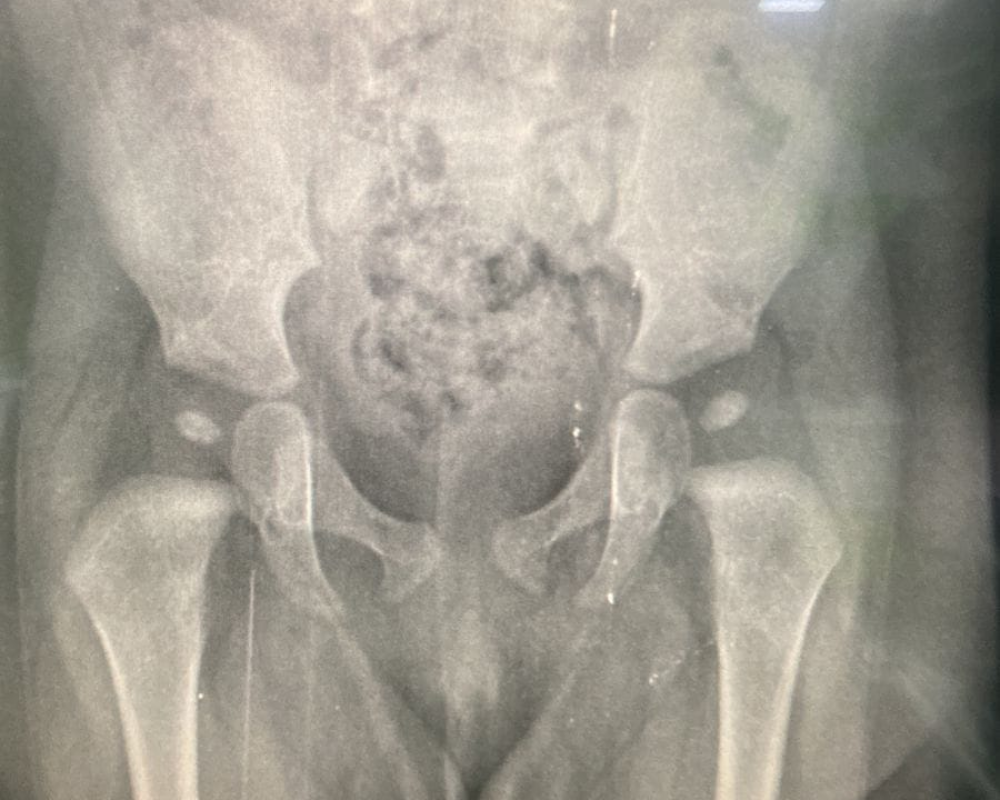

الخليل/ PNN/ إكرام التميمي -بالتعاون وبمبادرة من مركز الرشاد للأشعة، وملتقى آل التميمي بمدينة الخليل، وعلى مدار الأسبوع، انهى اليوم الخميس، مركز الرشاد للأشعة عشرات الفحوصات الطبية للمواليد الجدد، حيث تم إجراء تصوير  للحوض للكشف المبكر عن " خلع الولادة "، والذي استهدف الأطفال من كافة مناطق محافظة الخليل، وكما أعلن مركز الرشاد للأشعة بأنه سيجري يوم الأربعاء القادم بتاريخ_ 6\3\2024، هذه الفحوصات الطبية وصور الأشعة المجانية ولمن لم يتمكن من الإستفادة من هذه الفحوصات على مدار اسبوع الحملة، ولا سيما بأن مئات الحالات قد راجعت المركز وتلقت الفحوصات المجانية من كافة ارجاء محافظة الخليل.

ومن جانبه، قال: المدير الإداري للمركز الأستاذ محمد التميمي، نظرا لأهمية  تصوير  الحوض"خلع الولادة"، أجرينا هذه الفحوصات الطبية للمواليد الجدد .

وبدوره، اوضح المدير الطبي للمركز الدكتور وليد التميمي: بان هذا التصوير هام جدا، ومن خلال إجراء هذا الفحص يقوم الطبيب المتخصص في الأشعة بتقييم حالة الطفل ويبلغ الأهل في حال حاجة الطفل للمتابعة لدى اختصاصي العظام .

وأضاف: بأن التشخيص  المبكر  من شأنه أن يساهم في علاج الطفل بشكل اسرع  في حين أن التشخيص المتاخر قد  يستدعي إجراء  تدخلات جراحية، ومن شأنه ان يزيد من تكلفة العلاج على الأهل، ومن هنا تكمن اهمية الفحوصات الطبية في مراحل مبكرة للمواليد، حيث يجرى التصوير  التلفزيوني عادة على عمر الشهر  ويتابع المريض على عمر الأربع اشهر من خلال صورة الاشعة .